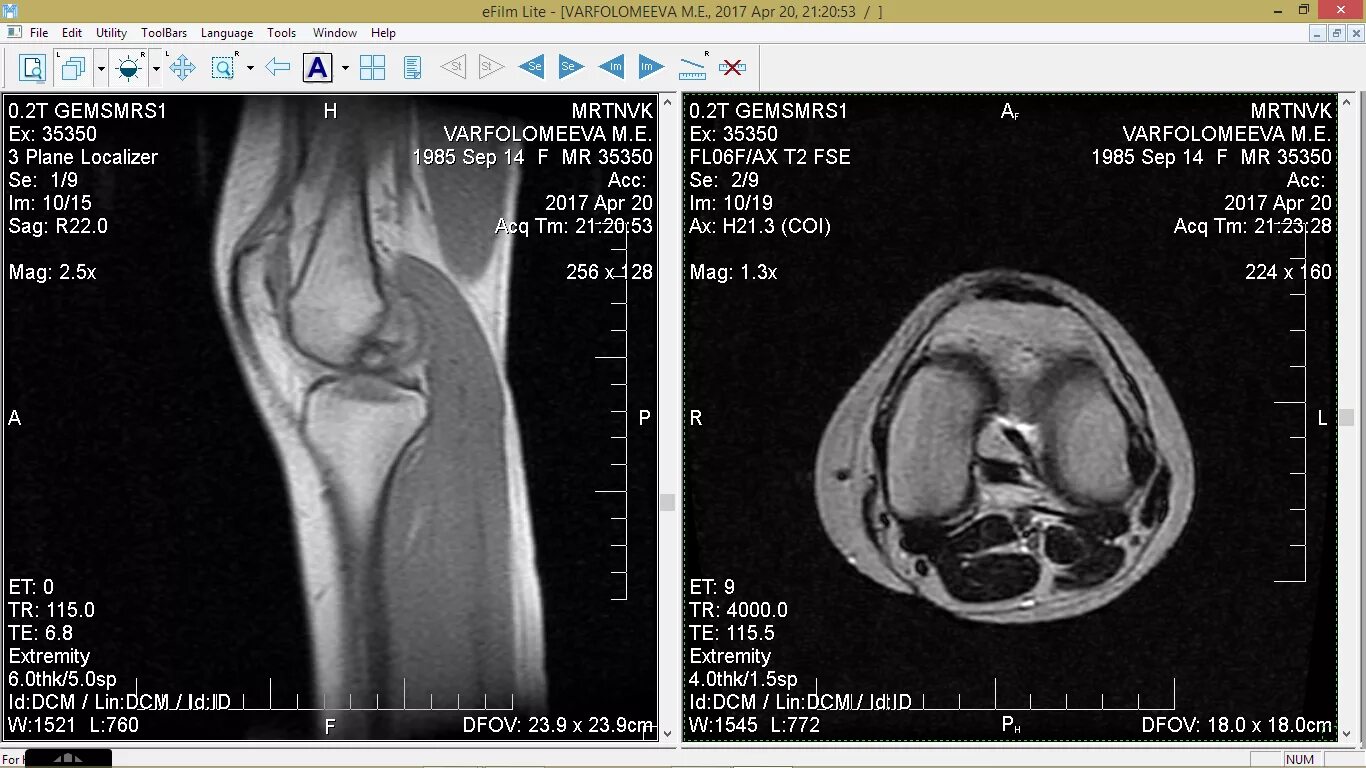

Сколько делается мрт коленного сустава по времени